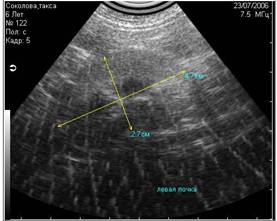

- вызванные плохим качеством выбривания кожи животного (Рис.3);

Рис3. Помехи, вызванные плохим выбриванием животного (продольные полосы слева). |